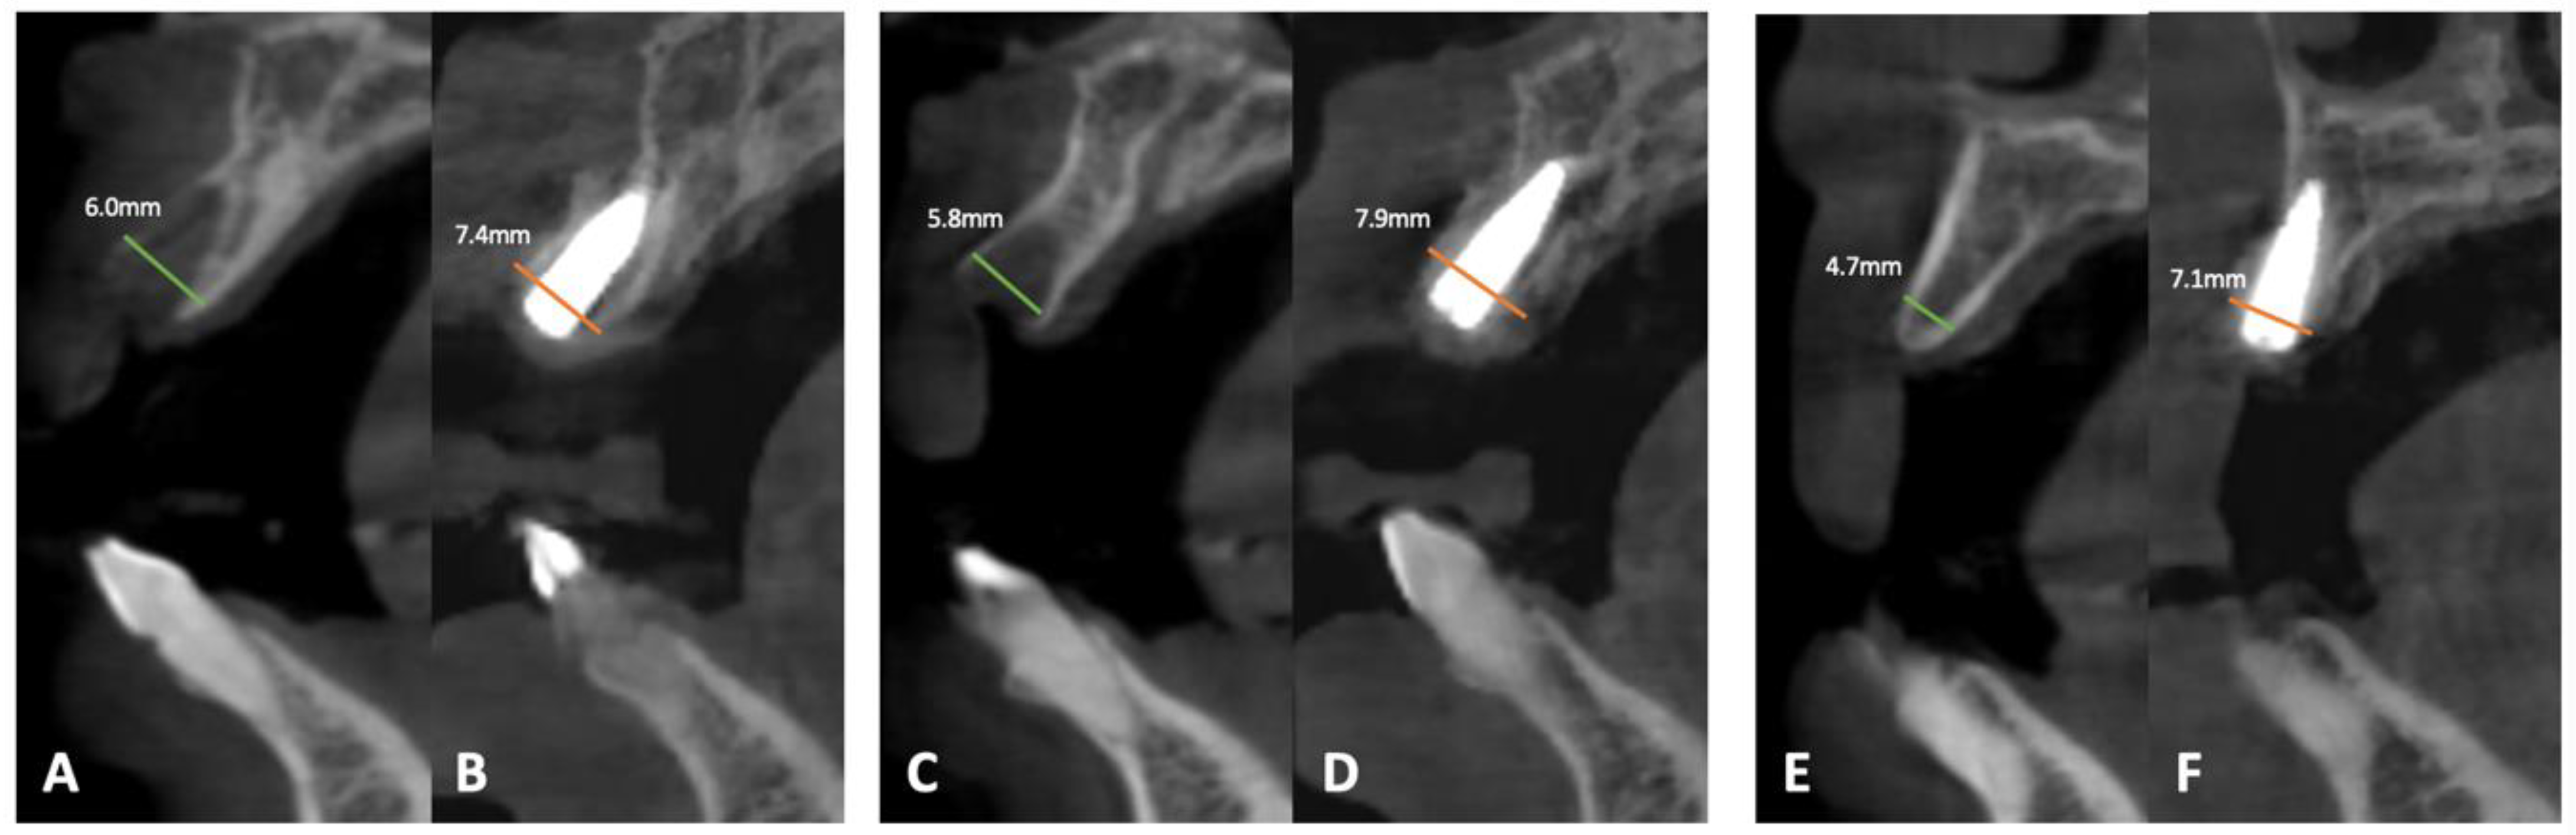

| Site | Baseline (mm) | 4 Months (mm) | Difference (mm) | |

|---|---|---|---|---|

| Buccal-palatal bone width | 21 | 6.0 | 7.4 | 1.4 |

| 12 | 5.8 | 7.9 | 2.1 | |

| 14 | 4.7 | 7.1 | 2.4 | |

| Gingival Thickness | 1.0 | 2.0 | 1.0 | |